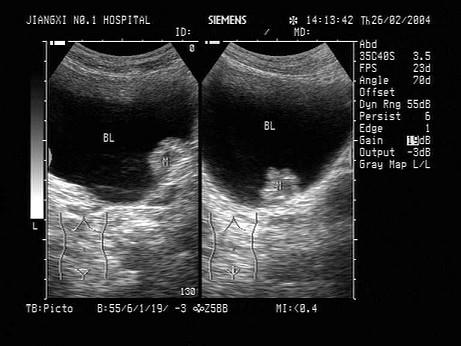

问题 患者,男性,70岁,出现无痛性血尿,如图所示,该病例最可能的诊断为?(?)

选项 A.膀胱结石 B.膀胱血块 C.膀胱异物 D.膀胱肿瘤 E.前列腺增生

答案 D